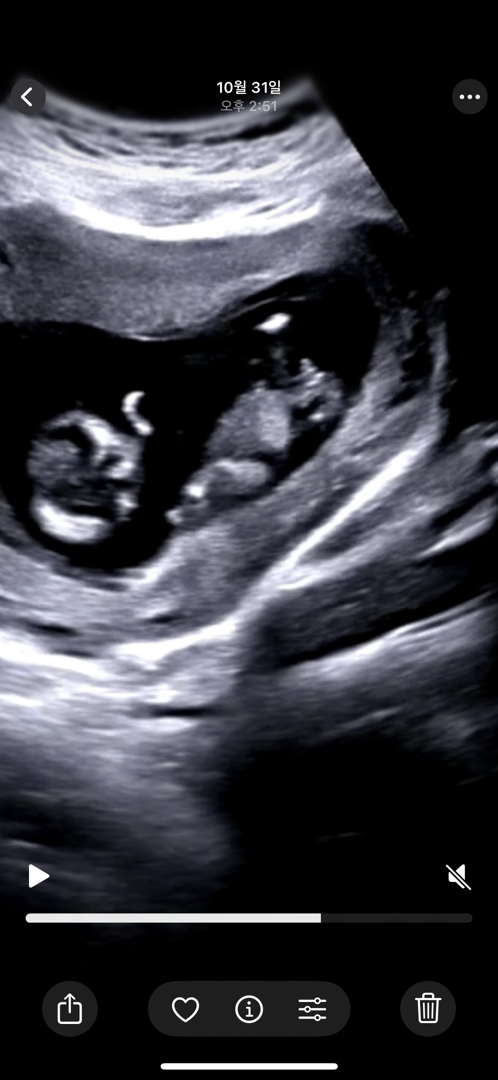

아들둘에 셋째인데 12주 봐주세요 ! ㅠㅠㅠ

아들일까요 …? 😂😂😂 댓글에 추가 사진 더 있습니다 !